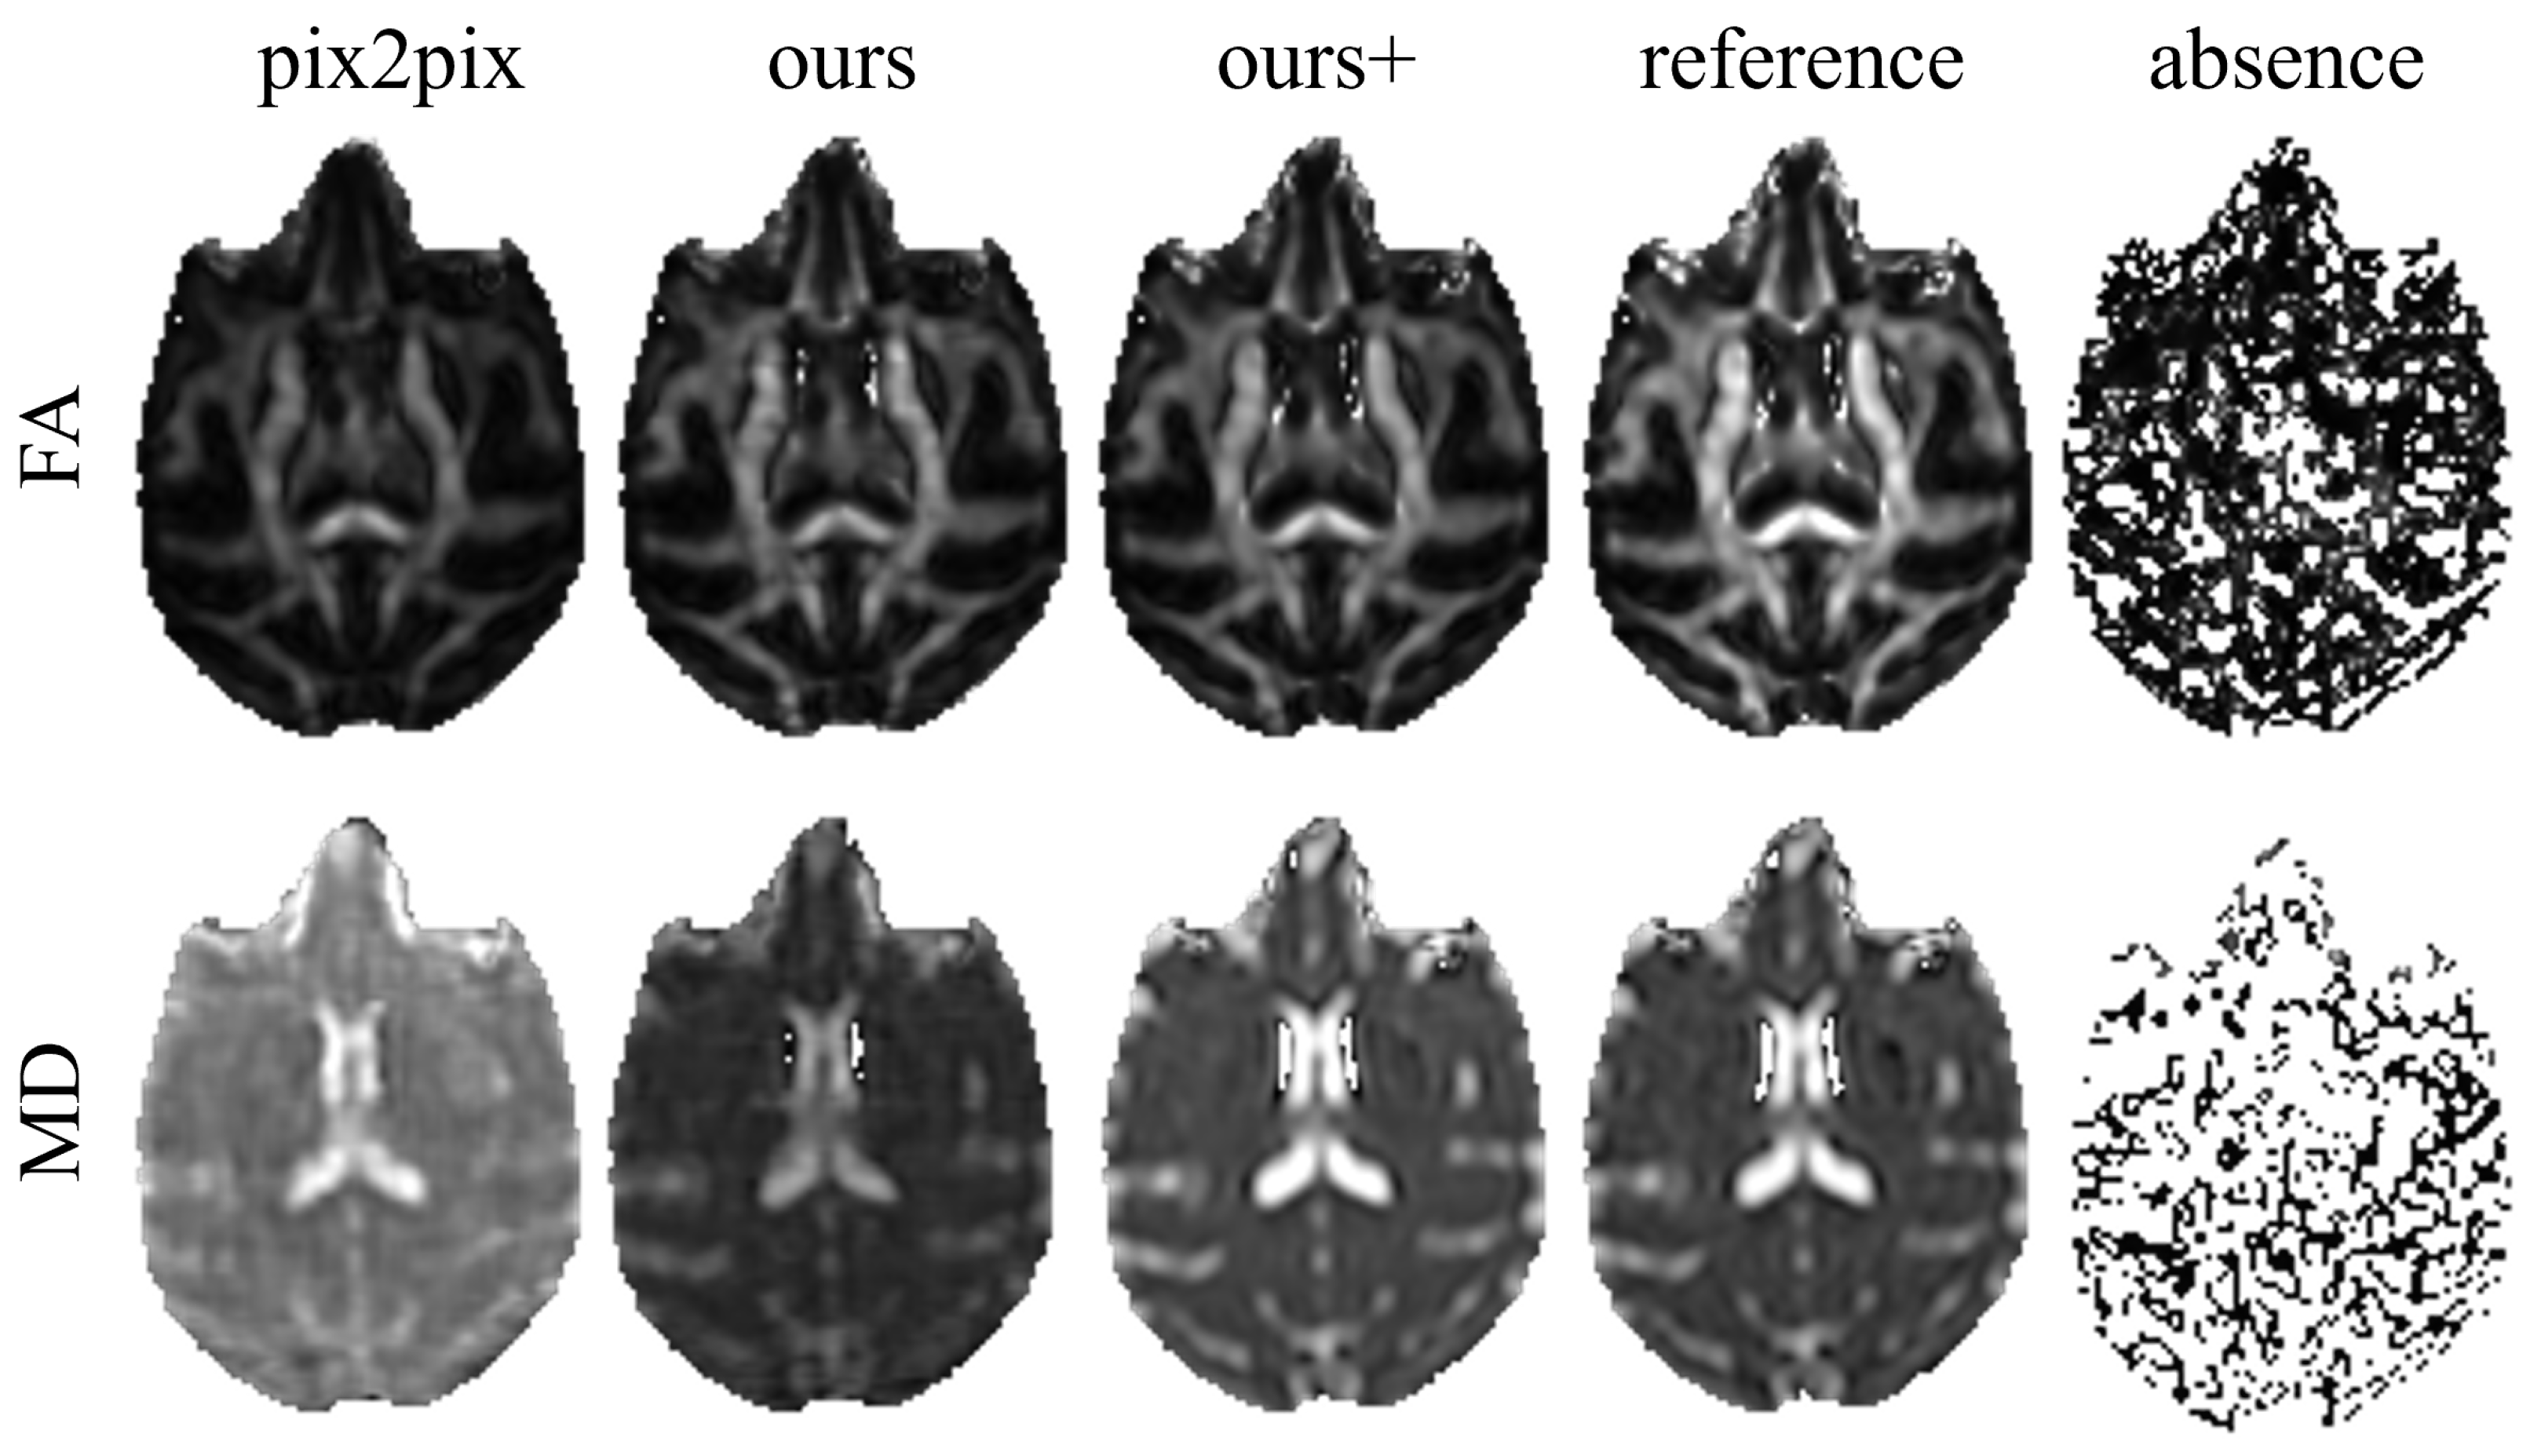

3.1. Comparison Experiments and Results

- Pix2pix [13] network adopts the U-Net architecture as the main framework of the generator.

3.2. Ablation Experiments and Results